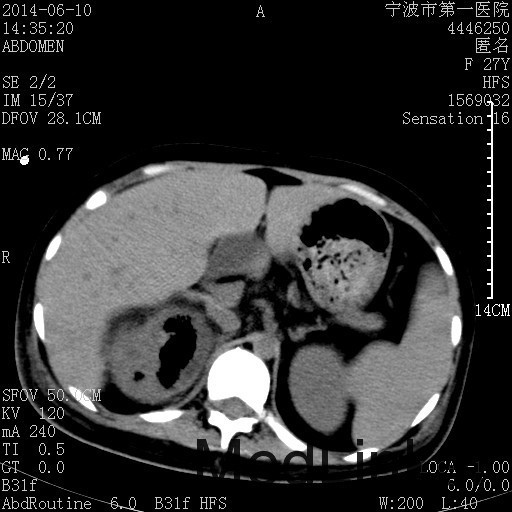

诊断为“气性肾盂肾炎,感染性休克,糖尿病酮症酸中毒” 血、尿、脓液培养均示“克雷伯杆菌” 入院第2天行“右双J管置入术” 入院第3天、7天行“右肾穿刺造瘘术” 入院1月行“右肾切除术” 术后顺利康复出院。

气性肾盂肾炎 • 气性肾盂肾炎是产气尿路病原体引起的急性肾实质坏死和肾周感染 • 大肠杆菌是最常见的病原菌,其次是克雷伯杆菌和变形杆菌 • 绝大多数气性肾盂肾炎患者合并糖尿病 • 死亡率19%至43%,单独的内科治疗通常是致命的,大部分患者最终需要行肾切除术 下一步治疗方案 • 拟行右肾切除术 • 患者经充分引流、抗感染治疗后现病情平稳,血糖控制良好 • 感染灶范围大,不能通过保守治疗消除,以往经验告诉我们保守治疗效果往往不佳 • 长期抗生素应用易引起真菌感染、伪膜性肠炎等并发症 • 若细菌对泰能耐药,后续抗感染治疗将十分困难 术前评估 • 手术风险评估(NNIS分级 2~3分) – IV 类手术切口(1分) – P3有严重系统性疾病,日常活动受限,但未丧失工作能力(1分) – T1手术在3小时内完成(0~1分) – 营养危险评分(NRS-2002) 营养状态评分3分+疾病严重程度评分2分=5分 围手术期治疗 • 术前、术中、术后血糖控制和调整 • 术后重症监护支持 • 感染控制和抗生素使用 • 手术前麻醉准备 患者最终在入院后1月行右肾切除术,术后康复出院。